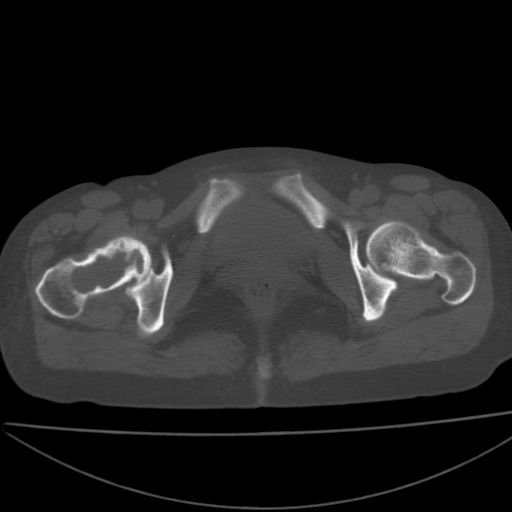

以下是引用xiaoniu在2008-9-6 8:22:00的发言:[br]右侧股骨颈囊性低密度,囊壁边缘硬化,中年妇女,首先考虑:骨囊肿。其次考虑动脉瘤样骨囊肿。[br][br][br][本贴已被 xiaoniu 于 2008-9-6 9:04:54 修改过]